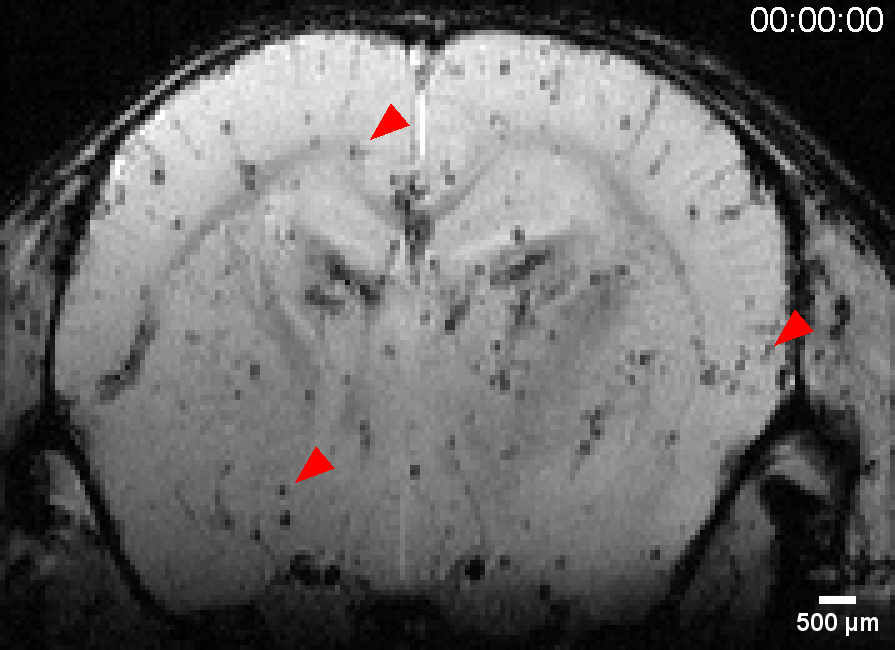

Die Arbeitsgruppe für Experimentelle Magnetresonanztomographie entwickelt und realisiert neuartige MR-Techniken, die die Grenzen der MRT in Bezug auf räumliche und zeitliche Auflösung sowie Sensitivität und Spezifität für physiologische, strukturelle und molekulare Veränderungen erweitern.Wir sind ein junges Team von rund 15 Personen aus verschiedenen Disziplinen, die sich dem Fortschritt der Magnetresonanz-Techniken und ihrer Anwendungen in der biomedizinischen Forschung und der klinischen Diagnostik widmen. Zu unserem Team gehören zwei Wissenschaftler, sechs Doktoranden, drei Techniker und in der Regel zwischen zwei und fünf Master- und Medzinstudenten.